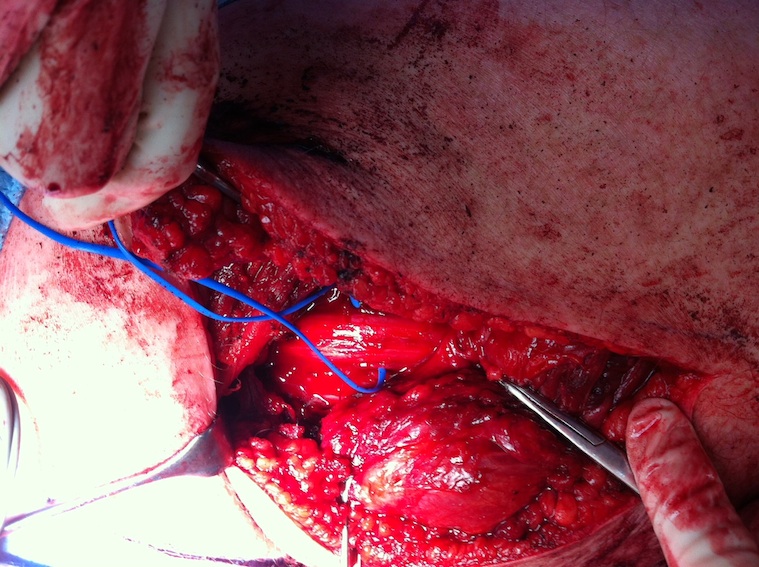

Sciatic nerve with blue vessiloops